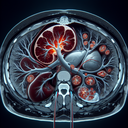

МРТ нирок

МРТ нирок — це магнітно-резонансна томографія, що використовується для отримання детальних зображень нирок та прилеглих структур. Цей метод допомагає лікарям діагностувати різні захворювання нирок, включаючи пухлини, камені, кісти чи запальні процеси. ### Коли може бути призначено МРТ нирок: - Підозра на наявність пухлин або кіст...